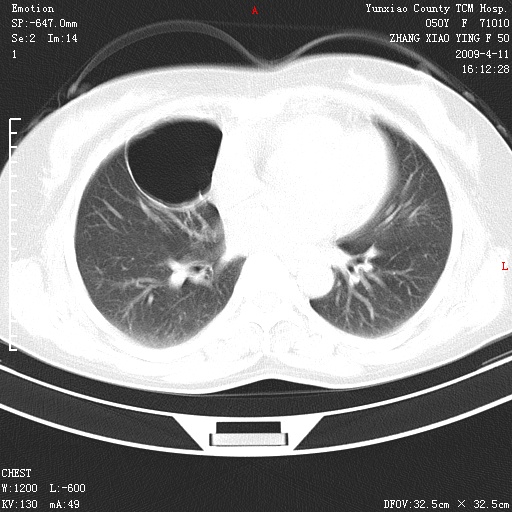

标题: CT19324:胸闷1周伴咳嗽 [打印本页]

标题: CT19324:胸闷1周伴咳嗽

肺囊肿并感染。

胸膜下肺大泡

病灶周围肺纹受压移位走行较柔和,余肺里实质均匀,纹理如常,肺间质无显著纤维化,支持考虑孤立性肺囊肿

考虑右肺中叶肺囊肿。